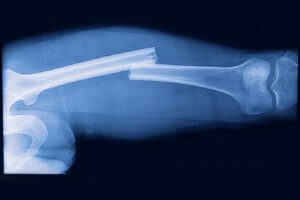

Травма со смещением

После перелома смещения происходят часто, куда пойдет отломок, зависит от места, высоты повреждения. Влияет на процесс и мышечный корсет — от кости бедра отходит много мышечных волокон.

Особенности:

- Если перелом приходится на верхнюю треть диафиза, верх отломка пойдет вперед и наружу, а низ назад и внутрь;

- В средней трети возможны любые смещения;

- Диафизарные переломы в нижней трети — верхняя часть кости съезжает вовнутрь, нижняя назад.